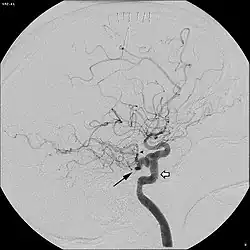

Angiogram demonstrating persistent trigeminal artery, as indicated by the black arrow.